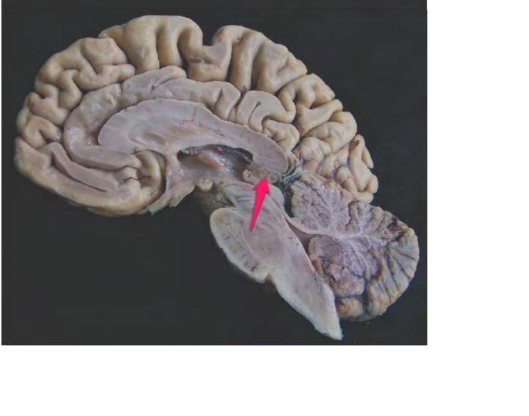

ventriculus IV